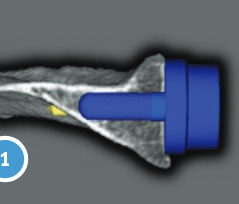

Inlay verus onlay

Centering guide wire passed

Depuy Synthes Delta Xtend

Center of inferior circle of glenoid

- metaglene needs to be positioned low to prevent inferior impingement and dislocation

- wire needs to angle perpendicular or slightly inferior / avoid superior tilt

- should exit scapula anteriorly about 3cm medial to glenoid

- ensure inferior screw will be in inferior good bone

- ream cartilage to subchondral bone

Metaglene / baseplate fixation

Screws as long as possible

- inferior screw - long into scapular pillar